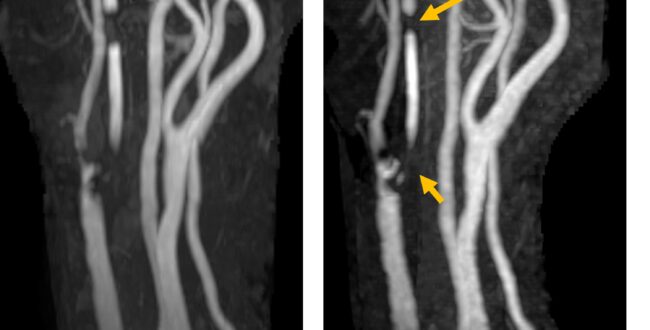

主幹も末梢も綺麗に撮りたい!Multi TE TOF sequenceのご紹介